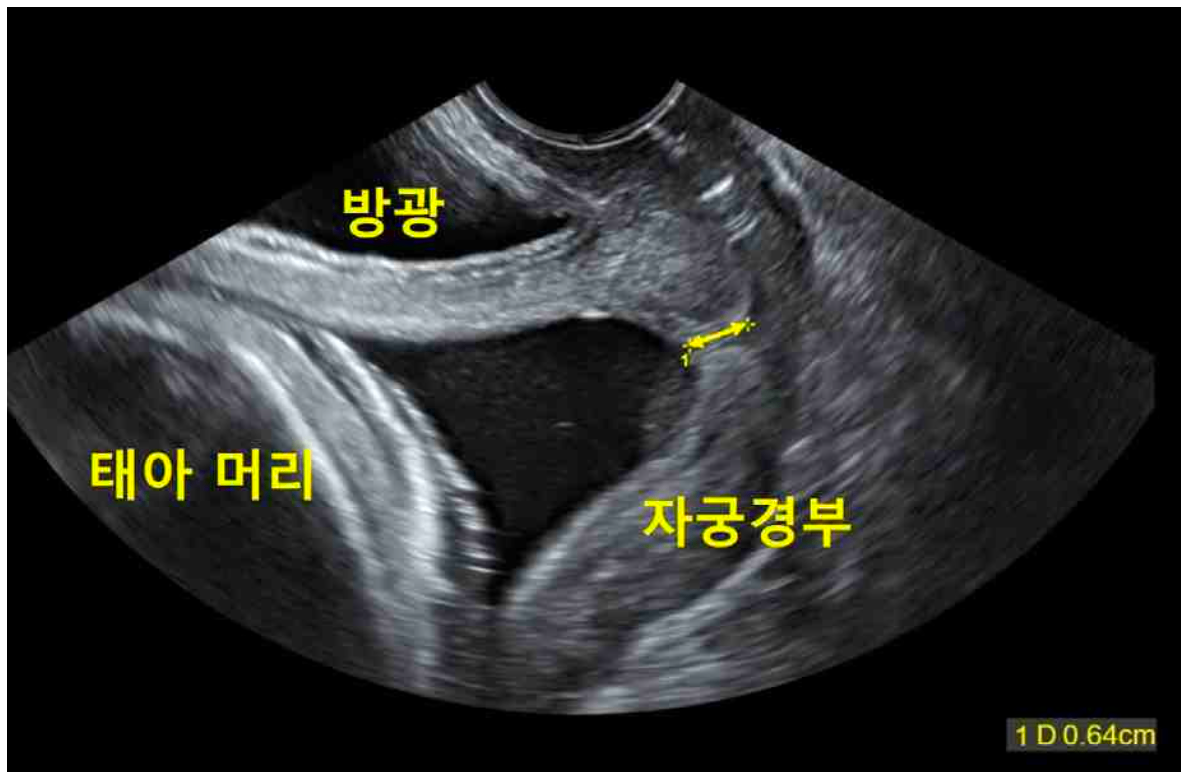

임신 20주인 35세 다분만부가 질분비물이 나와서 병원에 왔다. 2년 전 임신 31주에 조산했다고 한다. 혈압 110/70 mmHg, 맥박 90회/분, 호흡 20회/분, 체온 36.7°C이다. 골반검사에서 자궁경부는 닫혀있고, 나이트라진 검사 결과는 노란색이다. 초음파검사에서 태아는 두위, 예측태아몸무게 340g (50백분위수 331g), 양수와 태반은 정상이다. 자궁수축감시검사에서 자궁 수축은 없다. 자궁경부의 초음파검사 사진이다. 처치는?

US: 태아 두위, 체중 340g(>50p), AFI/placenta nl, cervical funneling, cervical length 0.64cm

조산 과거력이 있으며 자궁경부 길이 ≤ 2.5 cm이므로 자궁경부무력증 진단하, 24주 미만이므로 조산 예방을 위해 자궁경부결찰술을 시행한다.

• 현재 산모는 fetal CTG상 contraction이 관찰되지 않는데도 US에서 자궁경부길이가 0.64cm로 매우 짧으며, cervical funneling 또한 관찰된다.조산 과거력 + 짧은 자궁경부가 있으므로 자궁경부무력증으로 진단할 수 있다. 따라서, 조산 예방으로 위한 조치를 고려해야 한다.

• 자궁경부무력증이 있으며 24주 미만이므로 자궁경부결찰술(cervical cerclage)을 시행할 수 있다.